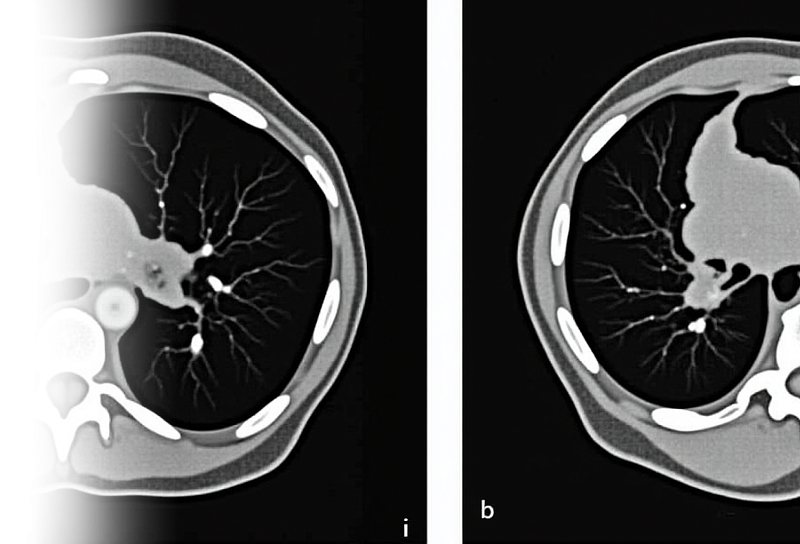

Компьютерная томография органов грудной клетки – важный метод исследования паренхимы легких, органов средостения, костного каркаса грудной клетки и мягких тканей.

• патологии паренхимы легких, средостения, мягких тканей грудной клетки;

• травматические изменения каркаса грудной клетки.